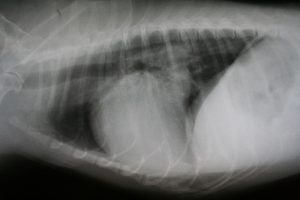

At Wheeling Veterinary Associates/ Glen Dale Animal Hospital in Glen Dale, WV, we are proud to be on the cutting edge of medical technology. Radiology is a technique and diagnostic tool we use to look inside the body in an entirely non-invasive way. X-rays allow us to create images of all the body’s organs. In other words, the use of radiology gives us a view of the internal organs in your pet’s body that we otherwise could not see. It’s a valuable diagnostic tool that helps veterinarians detect and prevent illnesses.

The images produced by digital radiography are of much better quality than film radiographs and can be manipulated digitally, giving us the best possible radiographic information to help us diagnose your pets.